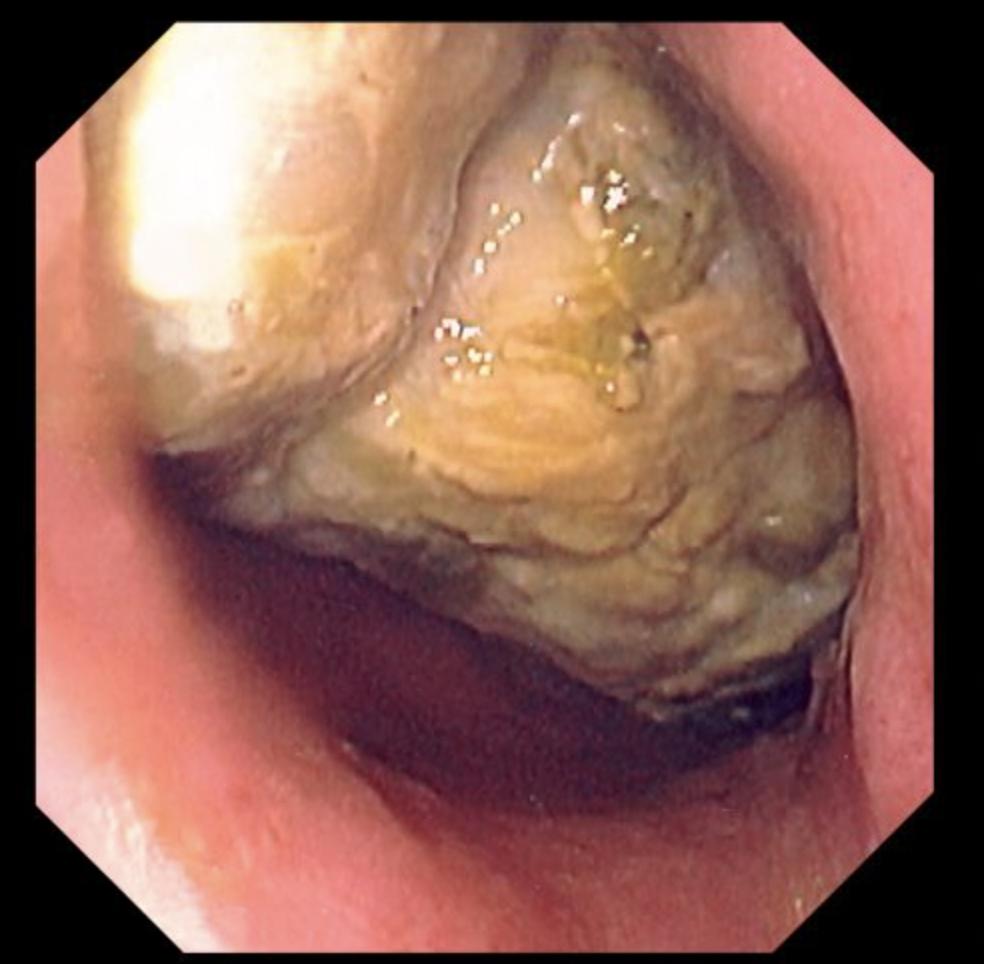

胃镜检查看到的胃石图片来源:默沙东诊疗手册

胃石在动物那儿很常见,有些是动物主动吃到胃里帮助碾磨消化食物的,有些则是难以消化的植物性纤维长时间在胃内积聚形成,比如牛黄。

人类不需要石头帮助胃消化,胃石一旦形成就有了麻烦。大部分人类的胃石是鞣酸结石,是鞣酸跟胃酸以及食物发生反应形成的。所以,空腹吃含有较多鞣酸的柿子就是胃石的主要原因。

胃里出现较大的石头可以让人有腹痛、腹胀,严重时还可能因为堵住胃出口导致梗阻,或者磨破胃壁导致出血穿孔。

胃镜检查发现胃石后可以直接进行碎石处理,把大块的胃石变成小块经口取出,也可以口服溶解剂溶石。可乐就是溶解剂之一,可乐里的磷酸对鞣酸石有一定的溶解帮助。所以,看到有人躺在病床上喝可乐也不必奇怪,那可能是在吃药治疗胃石呢。